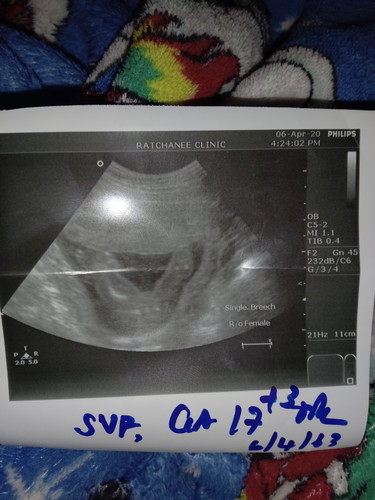

ว่าเป้นหญิงหรือชายค่ะ?

ผู้หญิงค่ะ ในรูปหมอบอก Female ค่ะ

ผู้หญิงค่ะ...มันขึ้นfemale